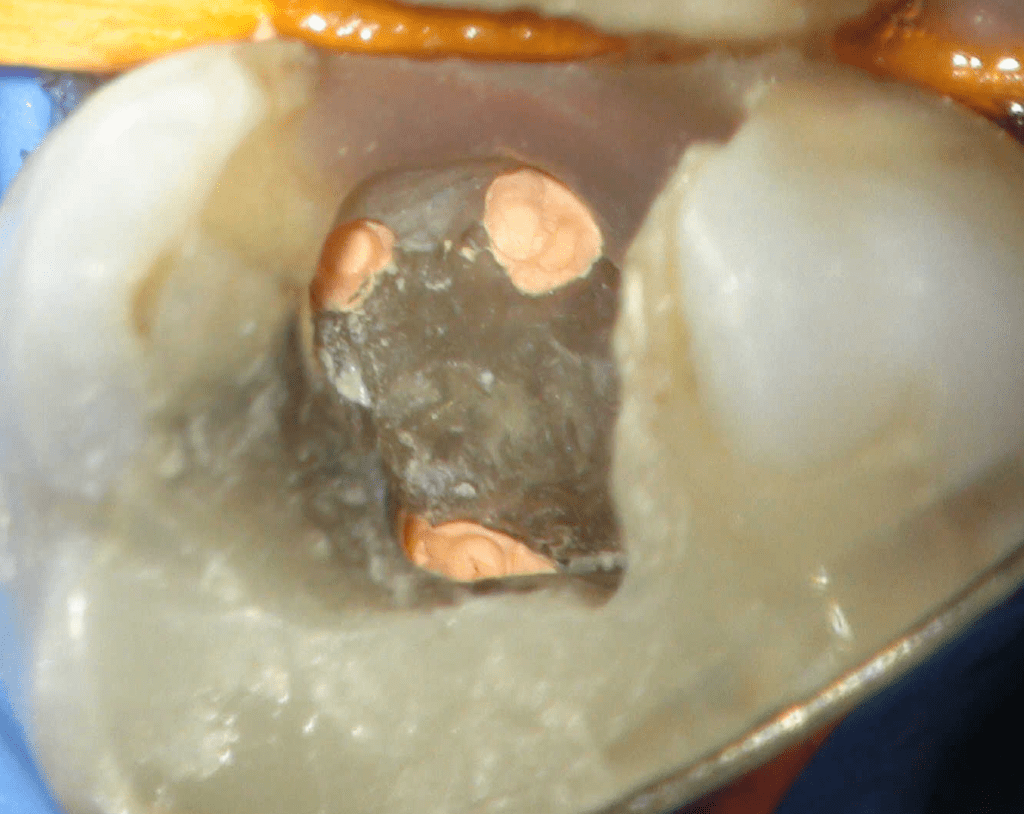

Reco preendo + 4 conductos molar superior

Reco preendo, 2o Molar superior